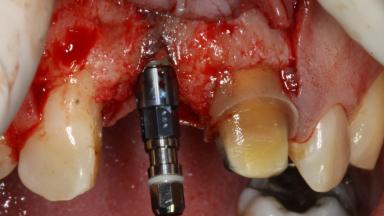

The patient presented with a failing tooth-supported fixed dental prosthesis with cantilever extension replacing the right maxillary central incisor. His chief presenting complaint was poor esthetics, in particular the dark discolored margin around the abutment tooth, the maxillary left central incisor. He reported a history of trauma at a young age, which necessitated the replacement of his maxillary right central incisor as well as root canal therapy of the adjacent left central incisor. The existing prosthesis had been in situ for over 20 years. The initial periapical radiograph displayed good proximal bone levels at the adjacent teeth and a wide incisive canal, which was a concern. The left central incisor presented a very wide root canal treatment with compromised radicular dentin thickness, which was a consideration in the decision between a new tooth-supported fixed dental prosthesis vs. an implant-supported prosthesis. After a lengthy discussion on the risks and benefits of both treatment options, the patient decided on a single-tooth implant replacement.

Bone Augmentation Simultaneous

Augmentation Materials Xenogenous

Bone Volume Deficient horizontally, allowing simultaneous augumentation